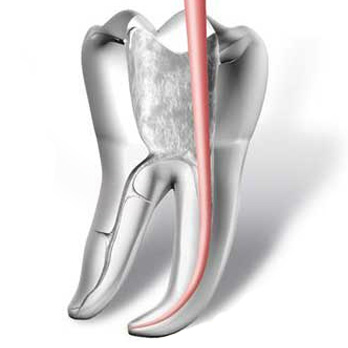

Los implantes dentales son un sustituto artificial de los dientes y sus raíces. Generalmente de forma roscada, los implantes poseen y brindan un aspecto y sensación similares a los dientes naturales logrando de esta manera una mayor comodidad, seguridad y confianza en su uso, respecto de otros métodos.